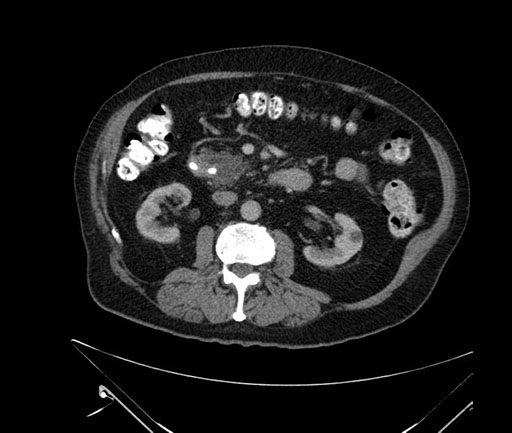

Imaging Analysis

Look through the patient's CT scan to identify any areas of concern for the necessary procedure.

Based on your CT findings, which issue(s) would give reason for "planned slowing down moment(s)" in this case?